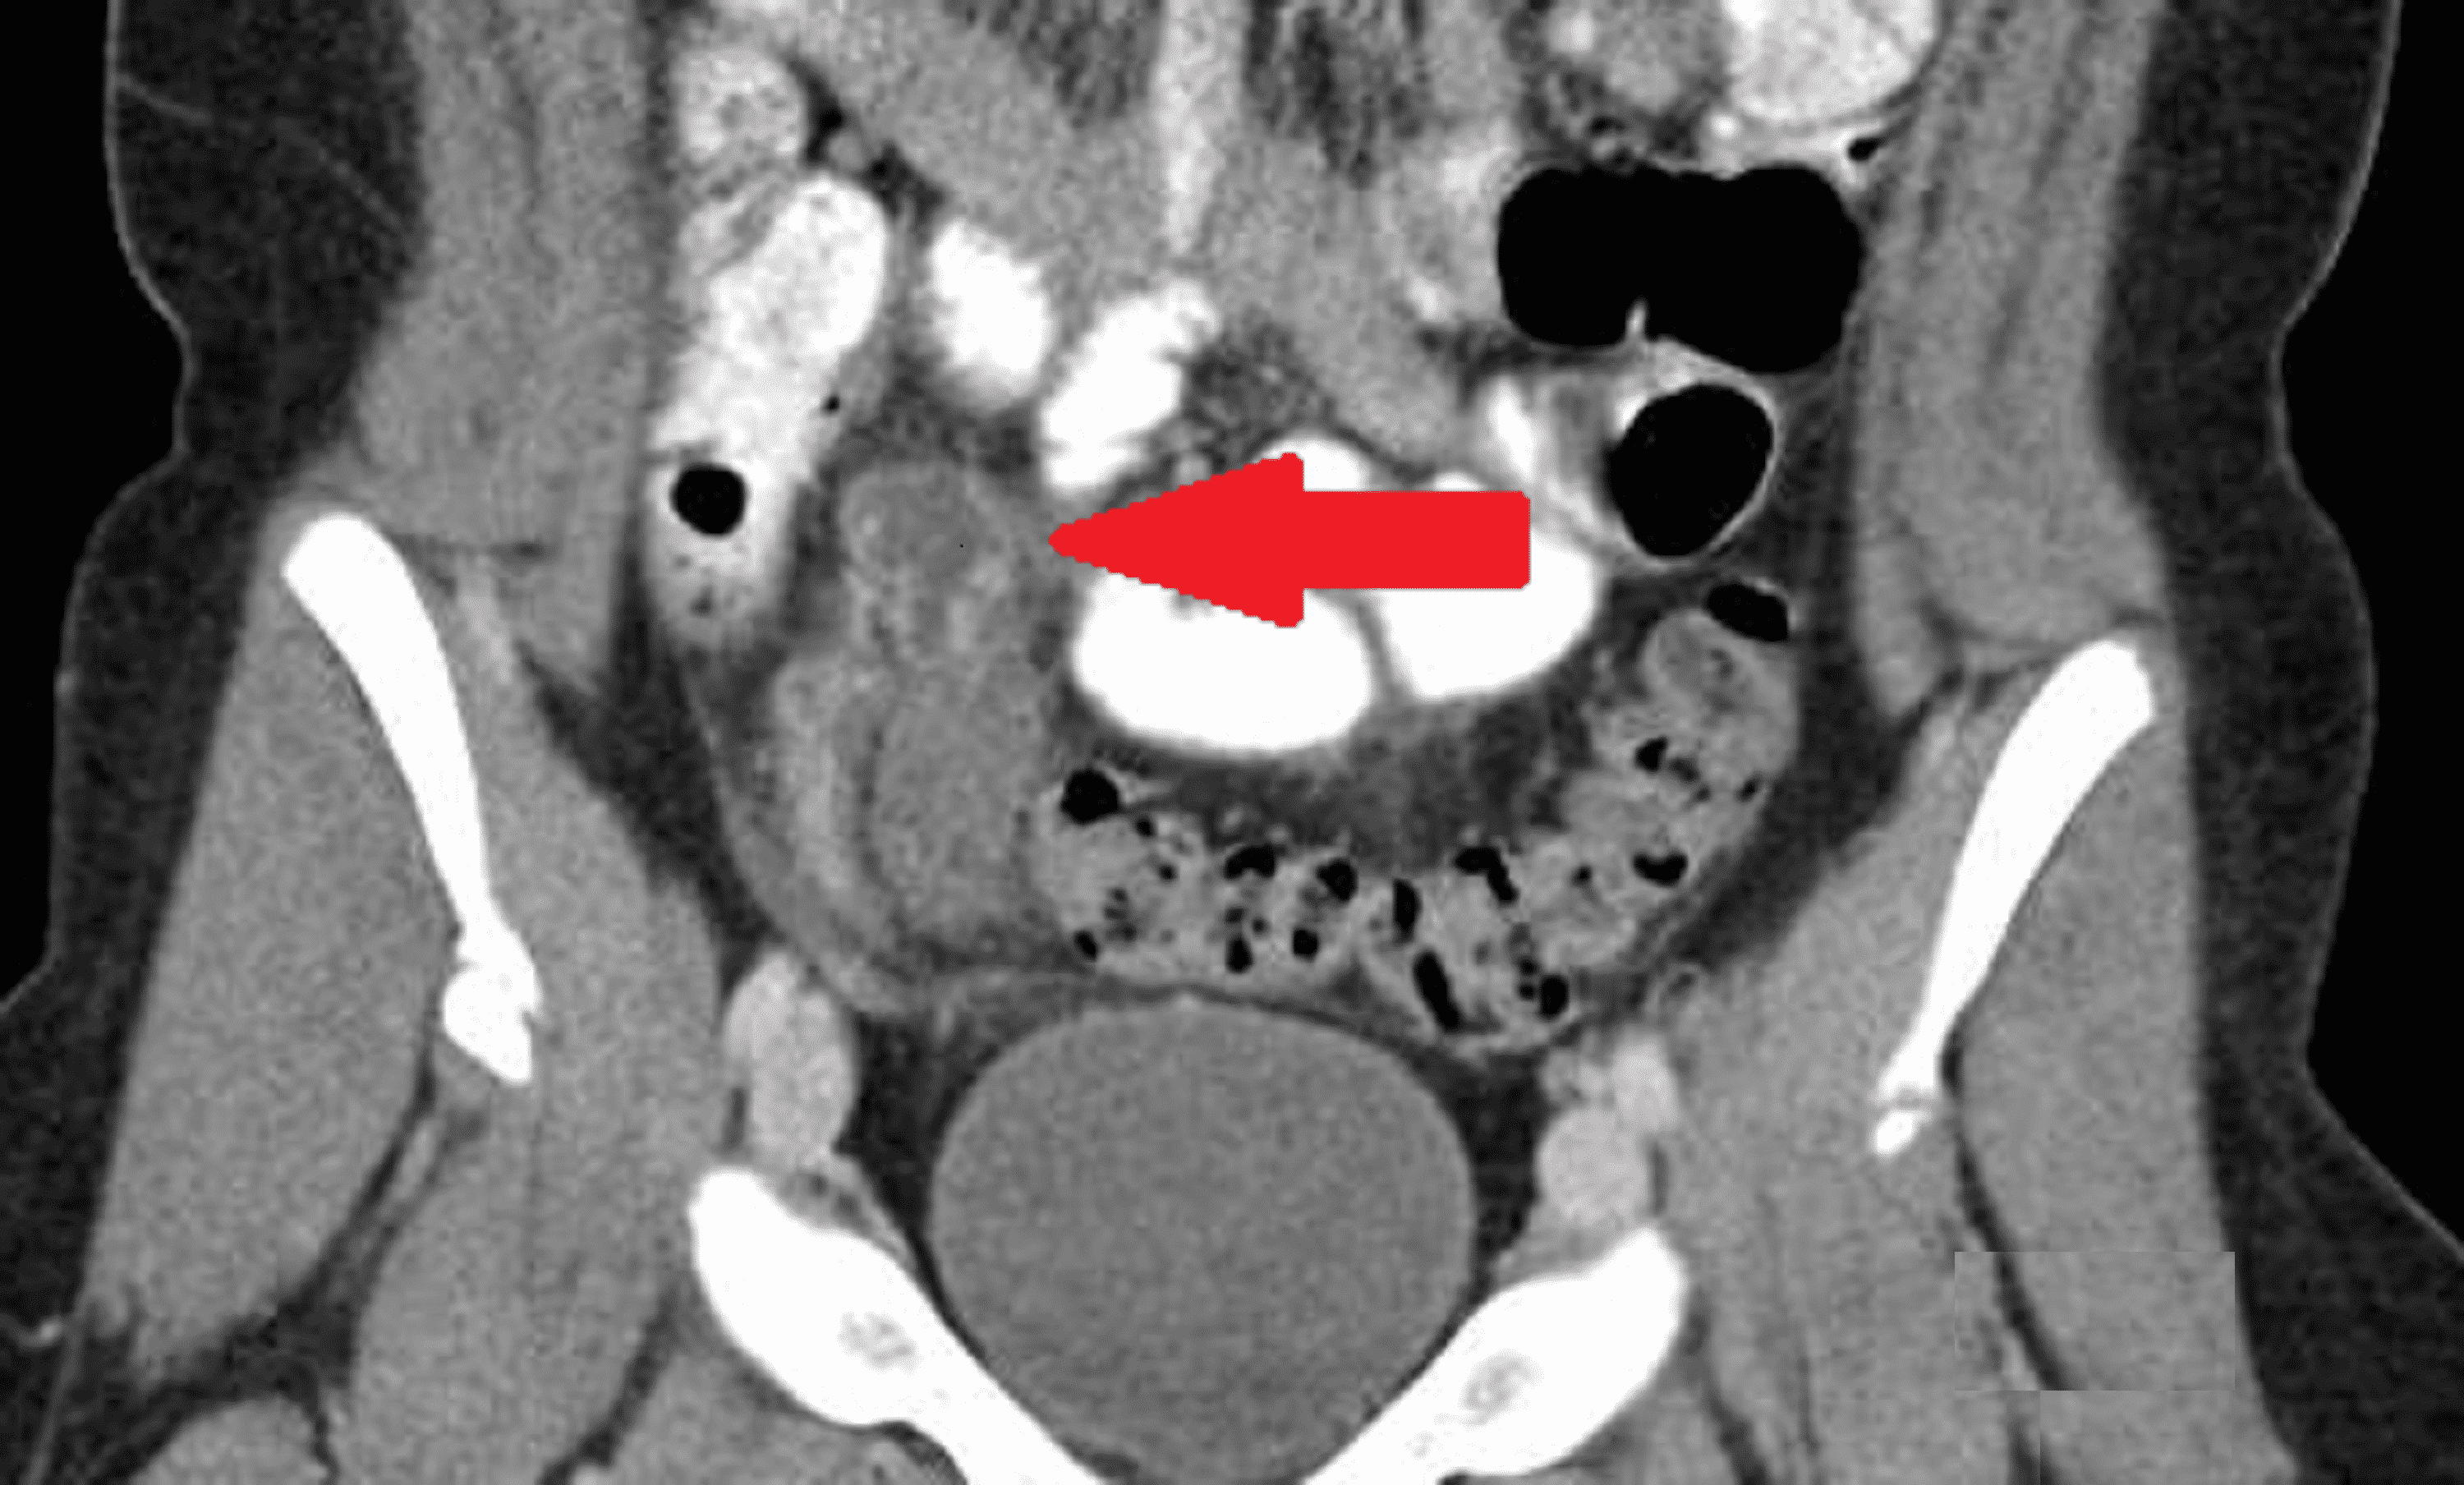

a, Urethral ballooning (arrow) and bladder trabeculation (arrowheads Spinning Top Ureter Spinning top urethras are named for the markedly dilatated posterior urethra presenting a. spinning top urethra (stu) denotes a particular urethral configuration that is a dilated posterior urethra mainly. spinning top urethra (stu) is a term used to describe a widened posterior urethra seen mainly in girls. the more common outlet dysfunction is the spinning top urethra. Spinning Top Ureter.